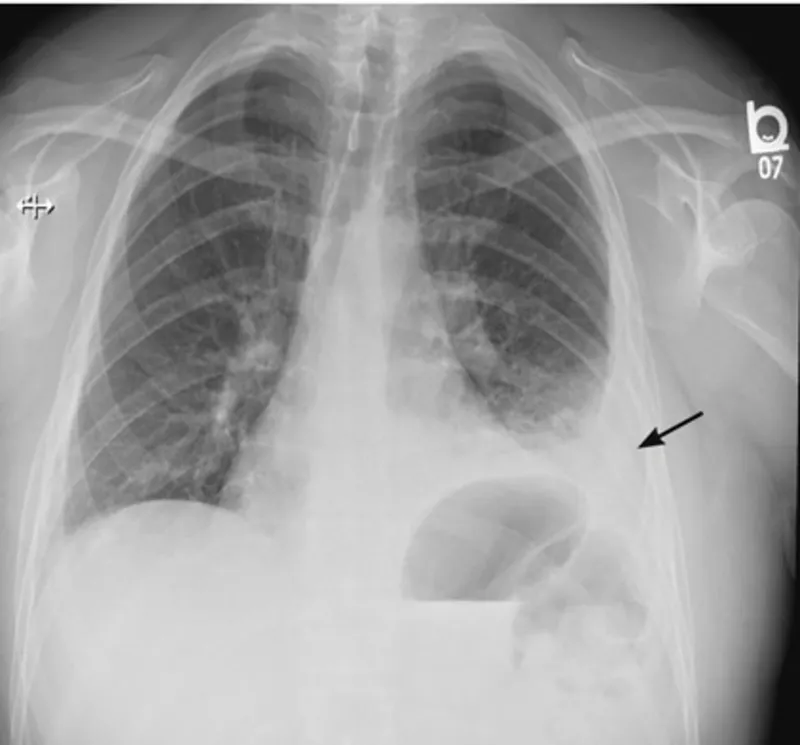

Air accumulation in the pleural space causes partial or complete lung collapse. Presents with acute dyspnea, pleuritic chest pain, and ↓ breath sounds.

⭐ Tension Pneumothorax: Characterized by mediastinal and tracheal deviation away from the affected side, hypotension, and JVD. Requires immediate needle decompression in the 2nd intercostal space, midclavicular line, followed by chest tube insertion.